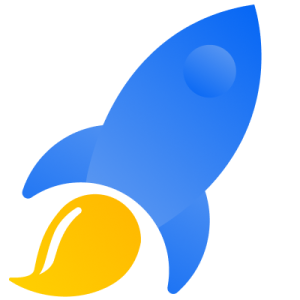

علاوه بر این، کلمات کلیدی تخصصی مربوط به انواع خاص CT Scan (مثلاً “سی تی آنژیو تبریز”، “سی تی اسکن ریه تبریز”، “سی تی اسکن شکم و لگن تبریز”) یا شرایطی که منجر به نیاز به CT Scan میشوند (مانند “تشخیص شکستگی با سی تی تبریز”) نیز میتوانند بسیار مؤثر باشند. استفاده از ابزارهای تحقیق کلمات کلیدی برای یافتن عبارات پرجستجو و کمرقابت ضروری است. سپس، این کلمات باید به صورت طبیعی در عنوانها، توضیحات متا، محتوای وبسایت و حتی نام فایلهای تصویری به کار روند.

- صفحات خدمات تفصیلی: برای هر نوع CT Scan (مثلاً CT Scan مغز، ریه، شکم، استخوان) صفحات جداگانه با توضیحات کامل، آمادگیهای لازم، و فواید آن ایجاد شود.

در حوزه سلامت، اعتماد حرف اول را میزند. بیماران باید به تخصص، ایمنی و کیفیت خدمات شما اعتماد کنند. برندینگ دیجیتال باید این اعتماد را تقویت کند. این کار از طریق شفافیت در اطلاعات (خدمات، تخصصها، قیمتها)، ارائه محتوای علمی و معتبر، نمایش گواهینامهها و مجوزهای پزشکی، و اشتراکگذاری داستانهای موفقیت (با رعایت حریم خصوصی) انجام میشود. برجستهسازی تکنولوژیهای پیشرفته مورد استفاده در مرکز CT Scan شما (مثلاً دستگاههای با دوز اشعه پایینتر یا قابلیتهای تصویربرداری خاص) میتواند یک نقطه قوت بزرگ باشد. طراحی وبسایت حرفهای نقش کلیدی در این اعتمادسازی ایفا میکند.